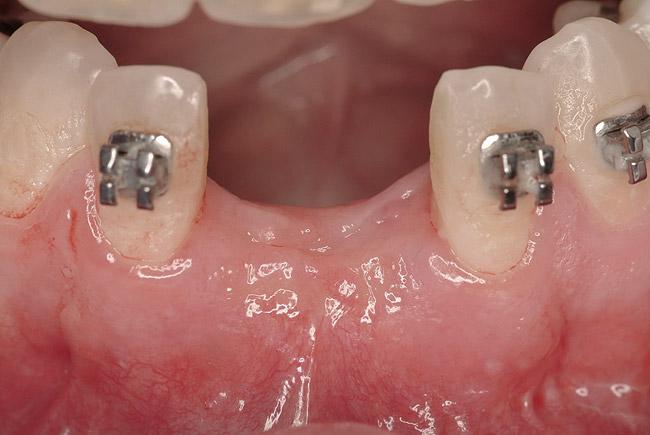

Figure 22  Surgical template, supported by the four remaining teeth and soft tissues. Sequential computer-guided implant placement was used to further stabilize subsequent implant insertions.

Figure 22

Figure 23  Implant placement in the Nos. 7, 8, and 9 positions. Because the mesh did not require removal, flapless placement was possible. Note that it is visually impossible to distinguish between which side (right or left) was augmented with rhBMP-2 alone and which side was grafted with rhBMP-2 plus PLGA mesh.

Figure 23